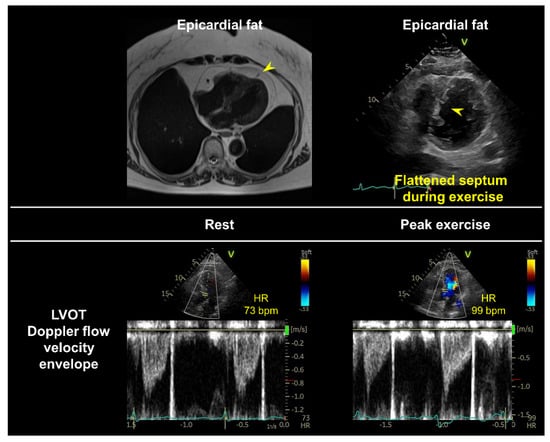

3.3. Stress Protocols, Image Acquisition, and Targeted Parameters

3.4. Interpretation of Test Results and Diagnosis of HFpEF